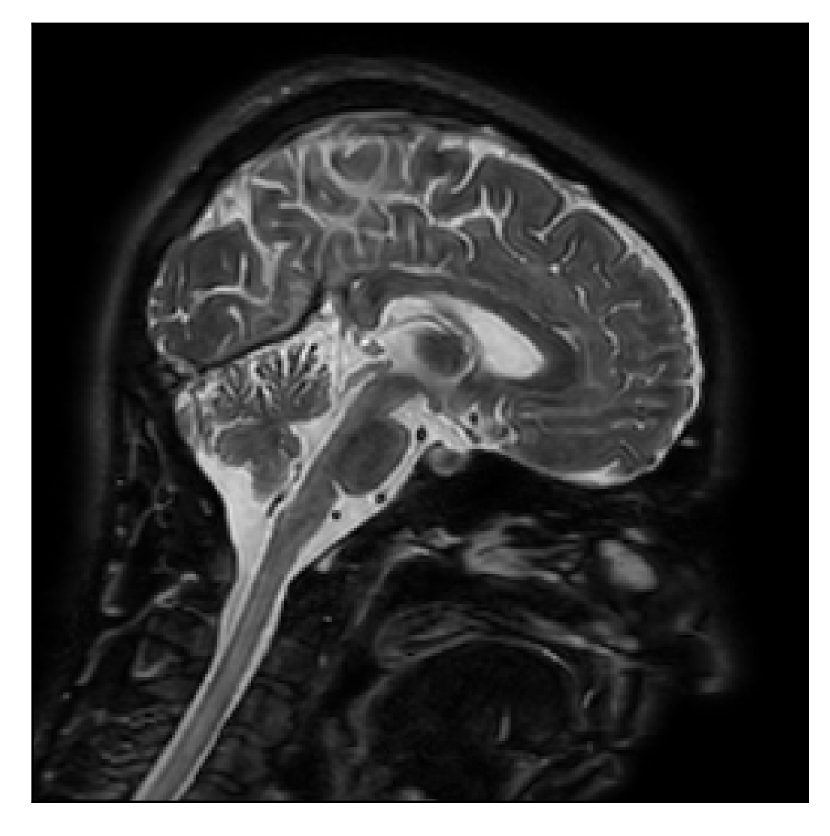

We consider three levels of motion corruption: (i) the volunteer moves once, (ii) the volunteer moves twice, and (iii) the volunteer moves five times. The volunteer is instructed to change its head position every time it is prompted to do so, and maintain that position in between instructions. We use T2-FLAIR-weighted contrasts as corrupted scans, with T1-weighted contrast as a reference (see Table 1 for further details). The corrupted acquisition employs randomized sampling.

| Section 3.1, Figure 2 | Sagittal | 23.94 | 27.95 | 0.7068 | 0.7936 |

| Coronal | 26.66 | 29.82 | 0.7653 | 0.8332 | |

| Axial | 25.40 | 30.16 | 0.7616 | 0.8490 | |

| Section 3.1, Figure 2 | T2-FLAIR | Completely corrected | Some blurring | No additional artifacts | Good grey white matter differentiation |

4.1 Experiment 1: robustness test

We gather the results for the robustness test described in Section 3.1 (volunteer 1) in Figures 2, 4, and 6 for motion corruption mechanisms associated to one, two, and five changes of position, respectively. Furthermore, we juxtapose the corrected images with varying degrees of corruption in Figure 8. We observe that the proposed method consistently ameliorates the corrupted scan. The quality indexes based on PSNR and SSIM show only a modest decrease in correction quality as a function of motion complexity (Figure 8).

Our experimentation based on volunteer data aimed at assessing the robustness of the correction quality with respect to motion artifacts of increasing complexity. In this study, we equated this complexity to the number of volunteer changes of pose during the acquisition phase. Clearly, this does not fully describe the complexity of motion encountered in practice in the clinic, but it only constitutes a preliminary step in that direction. Nevertheless, the results described in Section 4.1 support the indication that the retrospective motion correction of T2-FLAIR weighted images based on a T1 reference contrast is quite robust in terms of reconstruction quality, with only minor degradations in terms of contrast and resolution.

Sagittal

Coronal

Axial

Axial detail